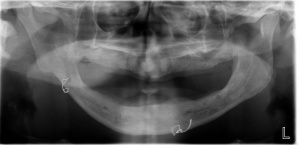

- Radiographs for Implants

- Guided Implant Placement